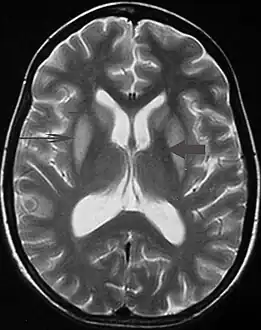

| MRI image showing hyperintensity in the pons with sparing of the peripheral fibers, in a person with alcoholism and an initial serum Na of 101 who was treated with hypertonic saline, and developed quadriplegia, trouble talking, and altered mental status. | |

It can be diagnosed clinically in the appropriate context, but may be difficult to confirm radiologically using conventional imaging techniques. Changes are more prominent on MRI than on CT, but often take days or weeks after acute symptom onset to develop. Imaging by MRI typically demonstrates areas of hyperintensity on T2-weighted images.[29]